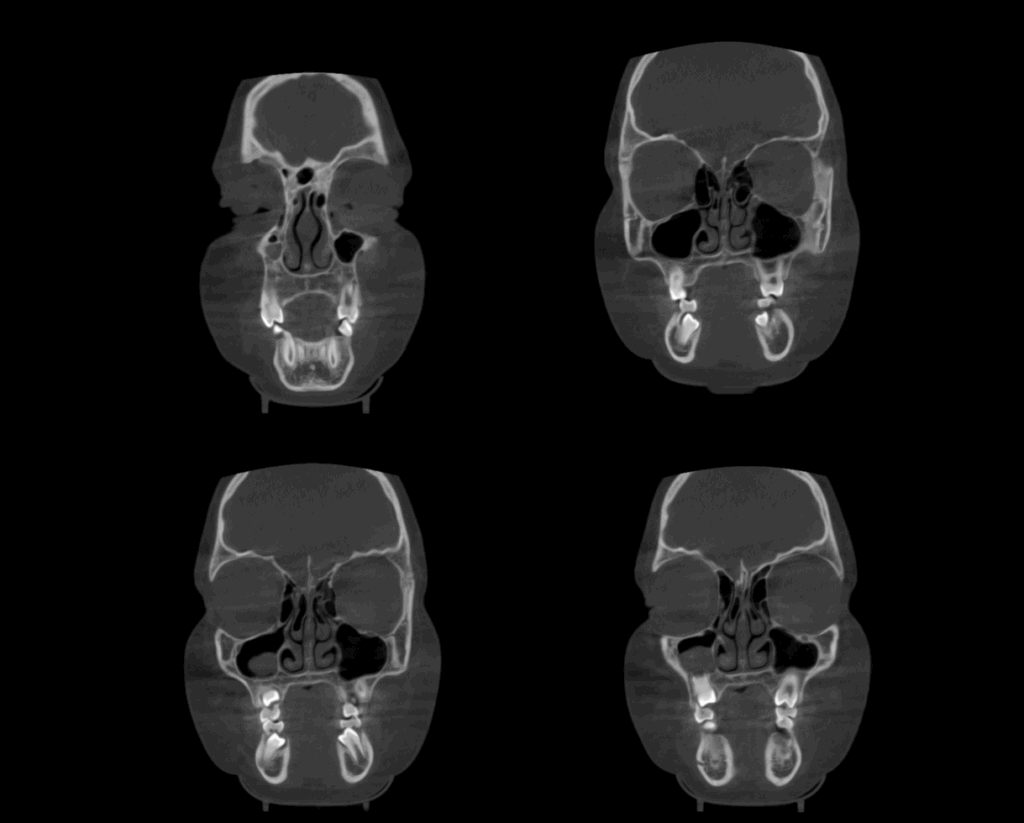

A la evaluación de la tomografía volumétrica (CBCT) en los cortes axiales (Figura 2) y transaxiales (Figura 3), se aprecia imagen hipodensa de forma globular en el interior del cornete medio derecho e izquierdo compatible con Concha Bullosa.

CORTES CORONALES